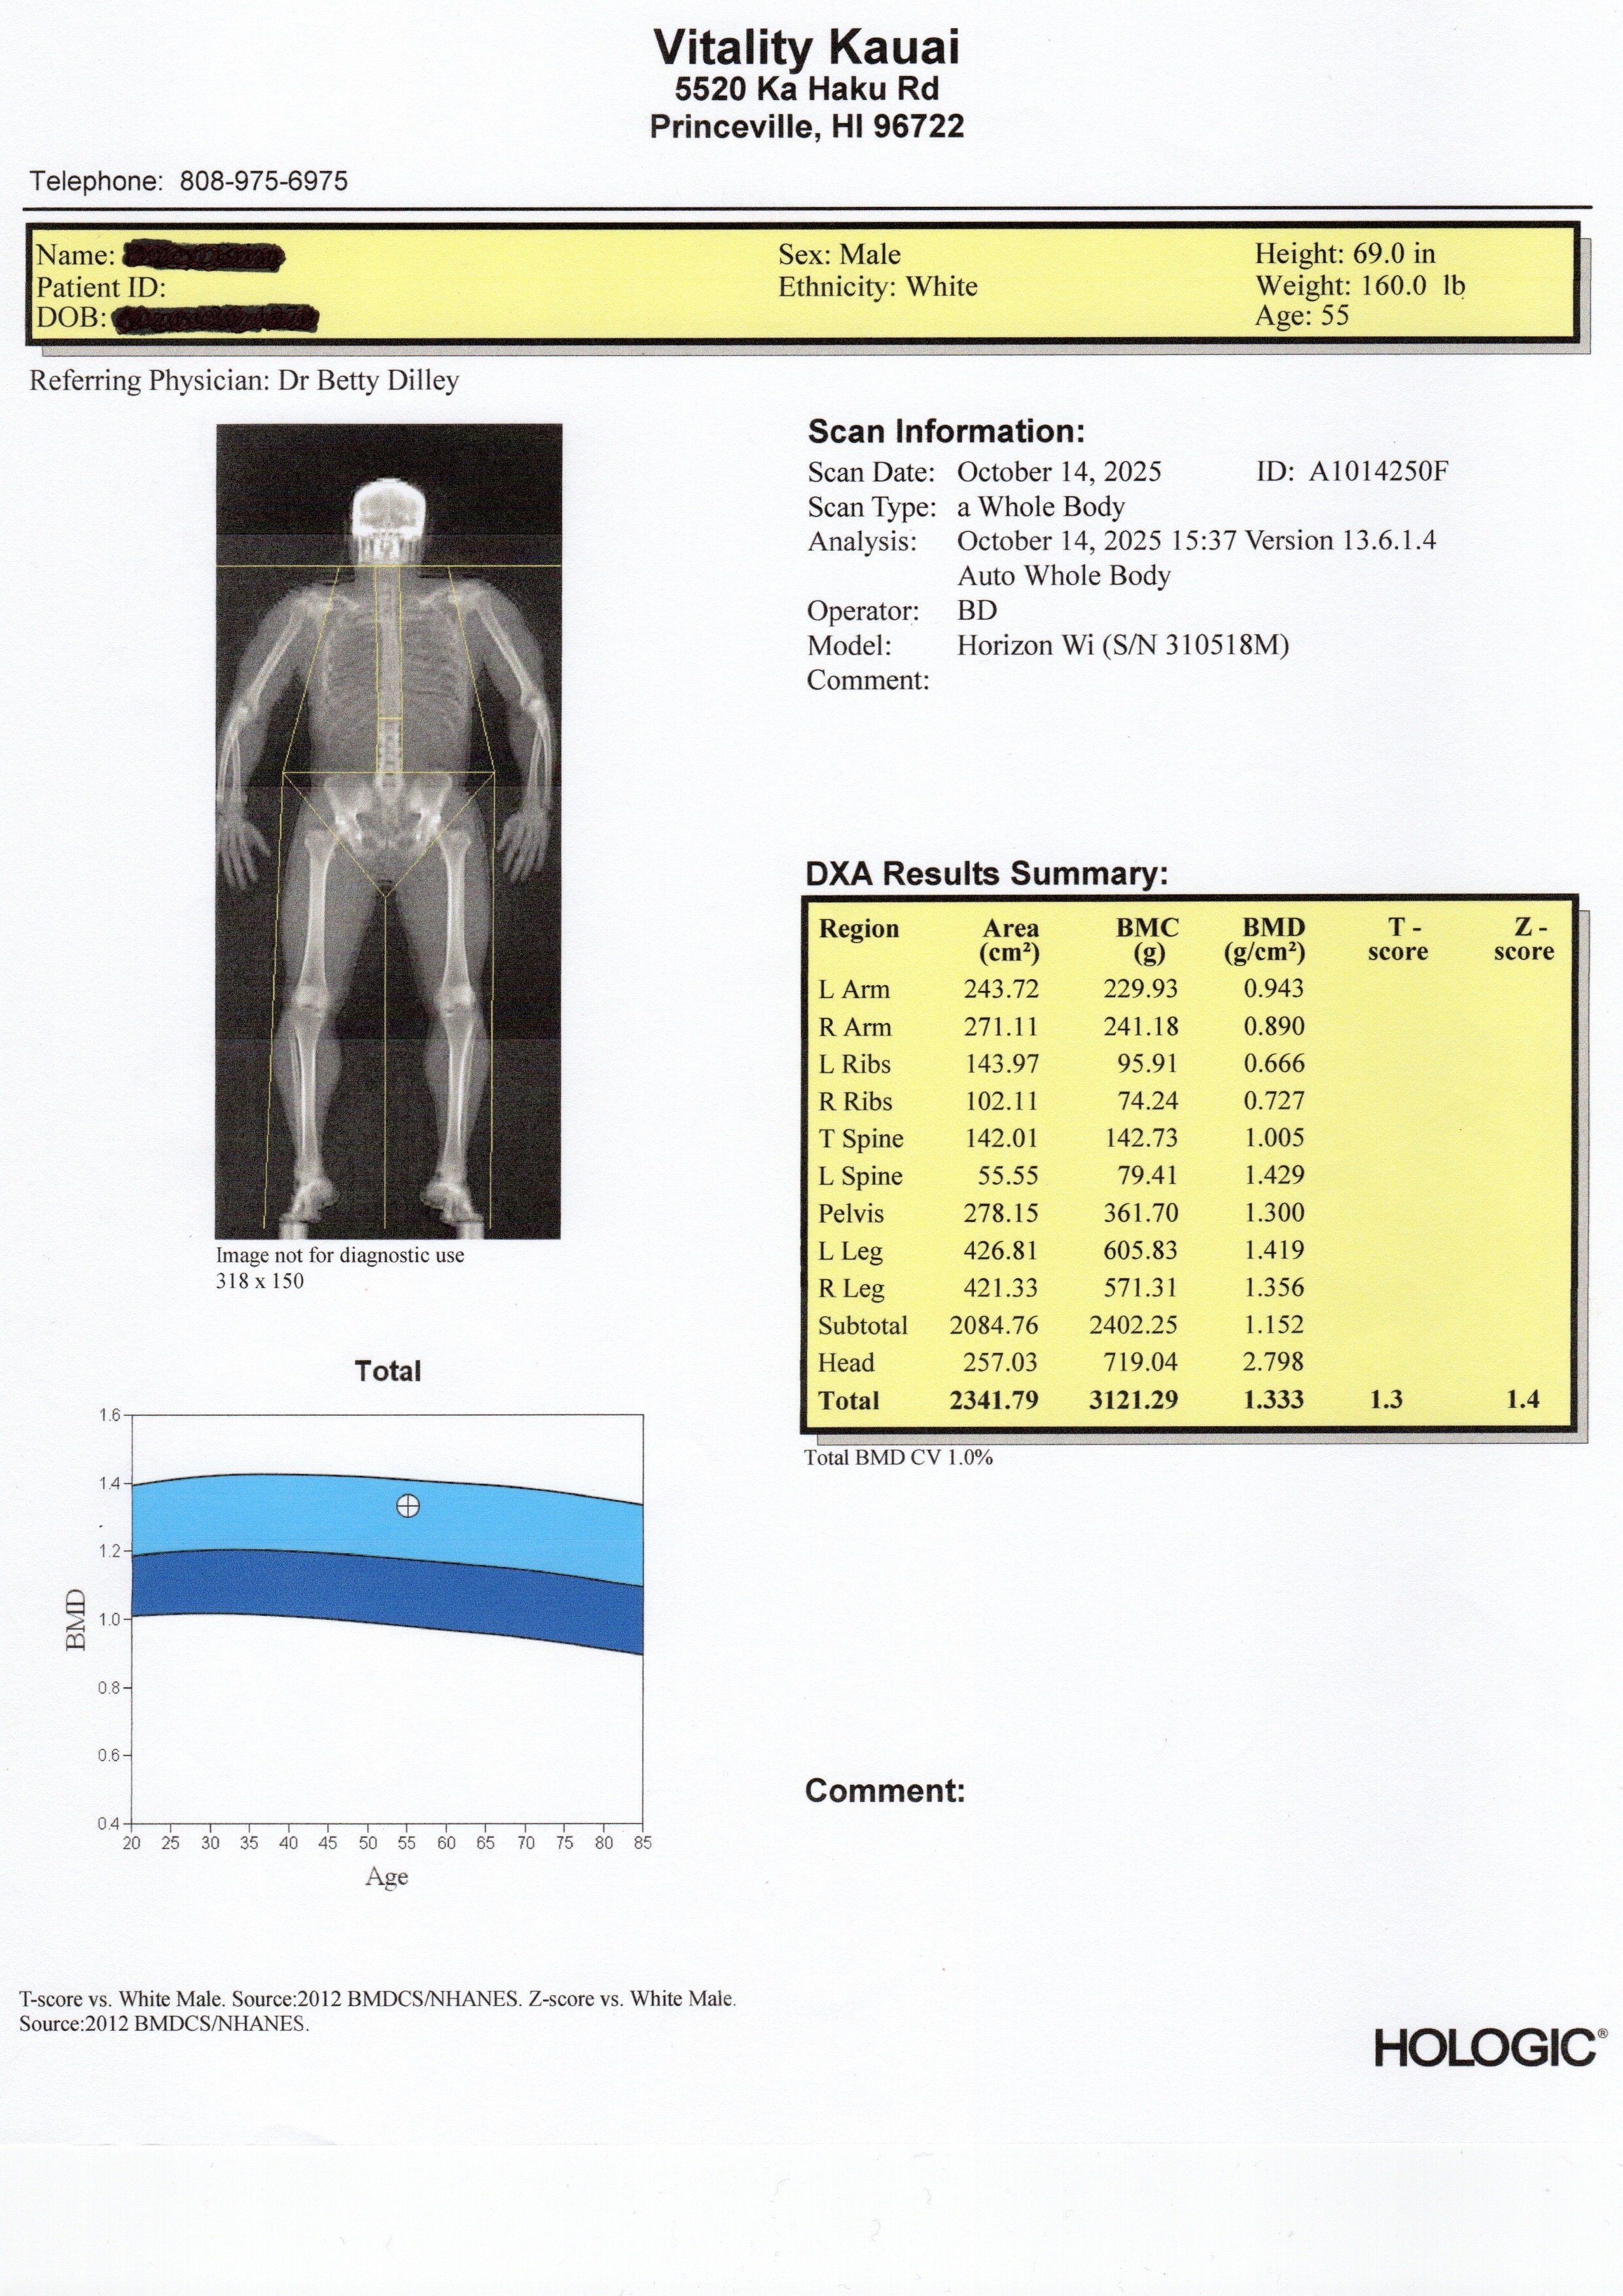

A Dexa (DXA) scan is the most accurate and comprehensive way to measure your body composition. Trusted by medical professionals, elite athletes, and researchers, this simple, non-invasive scan gives you the actionable data you need to transform your health.

In one 10-minute scan, you will learn your precise:

• ✅ Total Body Fat Percentage: Understand your true starting point and track real fat loss over time.

• 💪 Lean Muscle Mass: Ensure you're gaining strength and muscle, not losing it during your wellness journey.

• 🦴 Bone Mineral Density (BMD): Get a critical look at your bone health to assess your risk for osteoporosis and stay active for life.

• 🔬 Visceral Adipose Tissue (VAT): Measure the "dangerous" hidden fat around your organs, a key indicator of metabolic health.

• ⚖️ Body Asymmetry Analysis: Identify muscle imbalances to optimize your training, prevent injuries, and improve performance.